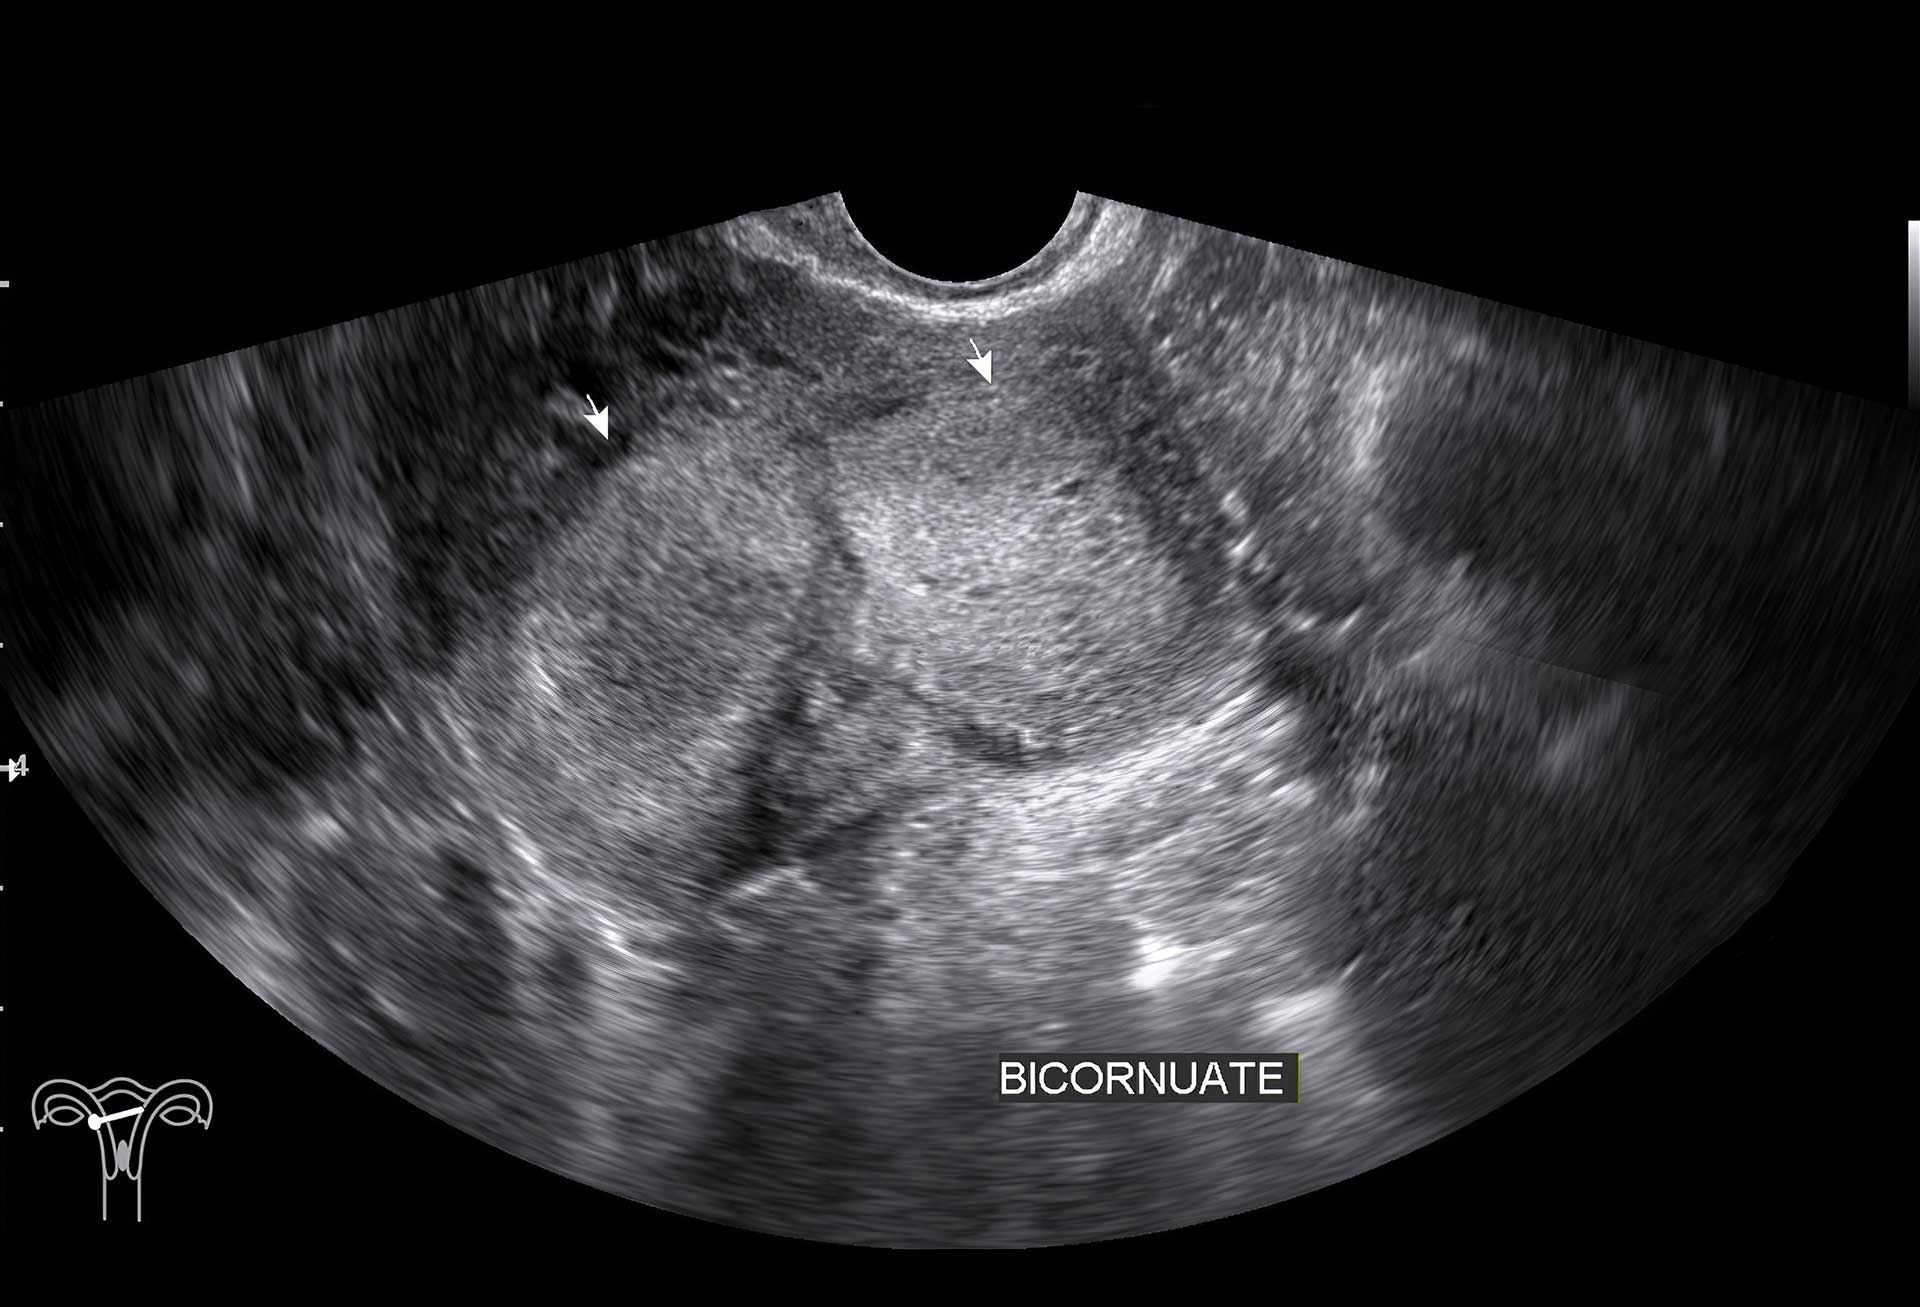

Questa metodica utilizza gli ultrasuoni emessi da una sonda appoggiata sull’addome (ecografia transaddominale) o inserita in vagina (ecografia transvaginale) attraverso cui si visualizzano su un monitor gli organi genitali interni, utero, ovaie e tube, quest’ultime visualizzabili solo se patologicamente dilatate (idro/sactosalpinge).

L'obiettivo è visualizzare la morfologia di questi organi e identificare eventuali masse atipiche o malformazioni.

Questa tipologia di esame diagnostico permette di valutare, mediante un'ecografia 3D, l'interno della cavità uterina e la possibile presenza di patologie ad essa collegate.

Viene eseguita quando si sospetta una malformazione o la presenza di polipi, fibromi o aderenze (sinechie).